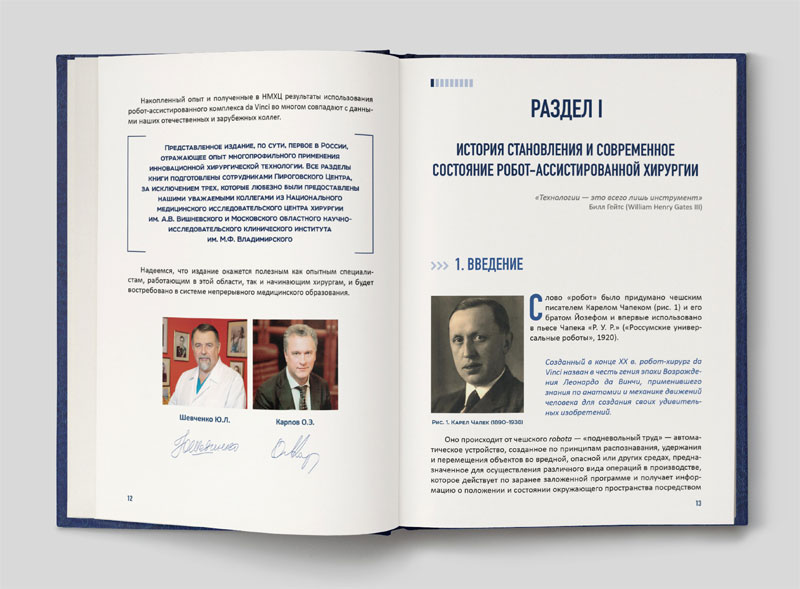

Торжество открыли основатель и президент Пироговского Центра, академик Юрий Леонидович Шевченко и генеральный директор, академик Олег Эдуардович Карпов.